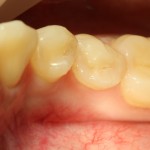

Вот фотография послеоперационной раны через пару дней:

Так, друзья, выглядит нормальная послеоперационная рана. Со швами я угадал. Это, кстати, Prolene 5-0.